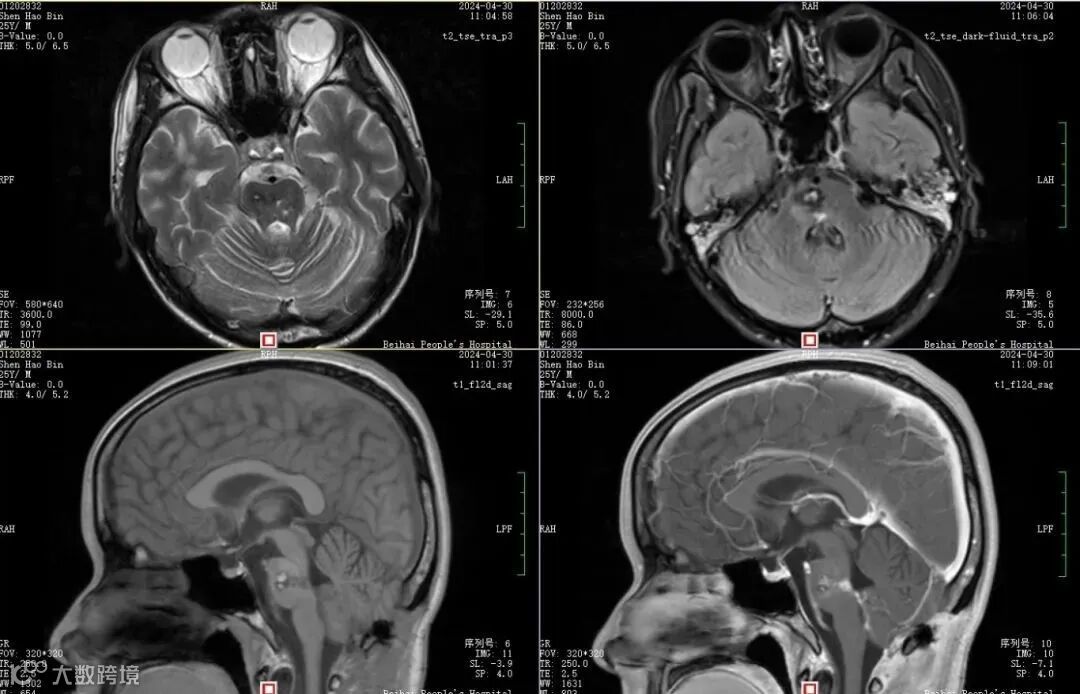

术后CT及磁共振提示病灶清除,术区呈术后改变